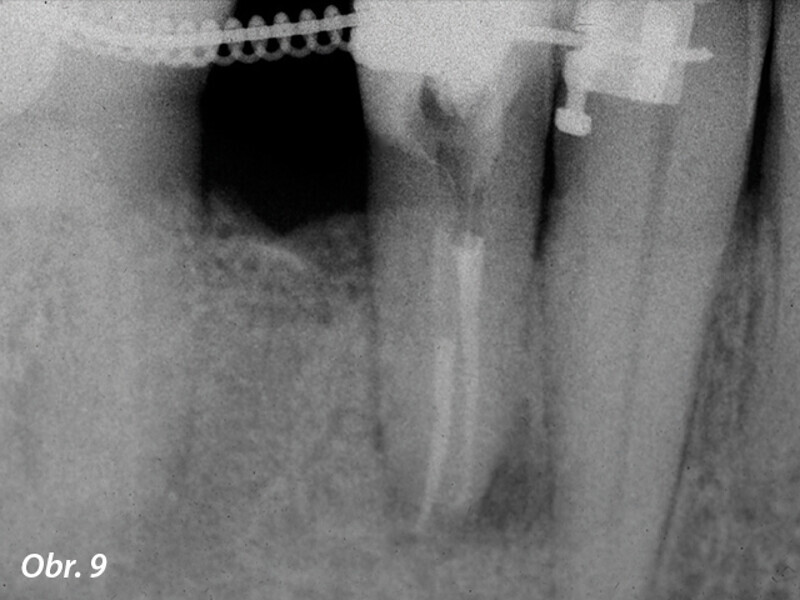

3D technologie v diagnostice a léčbě endodontických onemocnění